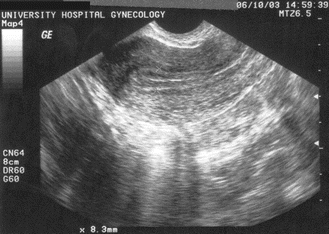

Fig. 5.2

Trilaminar appearance of the endometrial echo. Reproduced with permission from Lindheim SR, Uhler ML. In: Hurd WW, Falcone T, eds. Clinical reproductive medicine and surgery. St. Louis, MO: Mosby/Elsevier; 2007